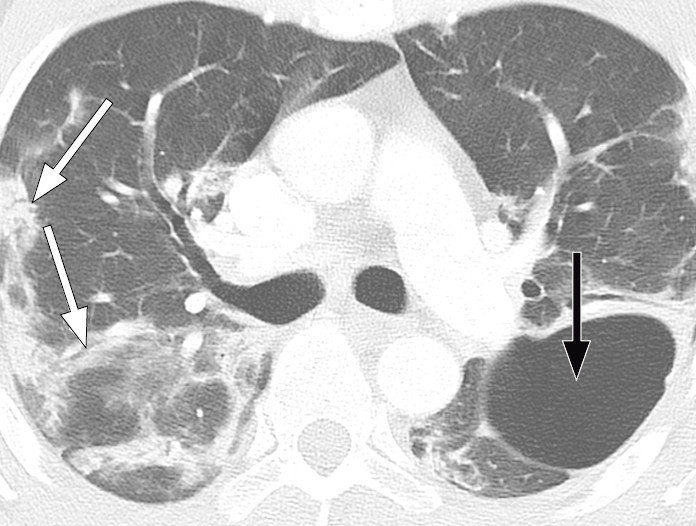

Typical CT findings vary with symptom duration and can be divided into three stages: an early phase, an intermediate phase that extends from 3–5 days after symptom onset, and a late phase.

There are not always CT findings the first few days after symptom onset. In a material with symptomatic, but unspecified patients, 56 % had normal CT findings within two days of symptom onset (12), declining to 9 % 3–5 days after symptom onset and 4 % 6–12 days after symptom onset. The frequency of findings varies with the severity of the disease. Initial diagnostic imaging yielded normal findings for 18 % in a cohort of patients who were not severely ill, but in only 3 % of patients who were (15). Typical CT findings are multiple, bilateral ground-glass opacities with peripheral distribution, most frequently located in the lower lobes. In the intermediate phase there are increasing amounts of consolidation and affection of several lobes, and increased septation with crazy paving as sign of interstitial affection. In the late phase there is increasing total extension, but ground-glass opacities and consolidation are still the dominant findings (12, 16). Figures 4, 5 and 6 show typical CT findings in different phases of COVID-19.

In a severe disease course, distortion of the lung architecture, traction bronchiectasis, enlarged lymph nodes and pleural fluid can be detected. These are findings that are not specific for COVID-19 (17).